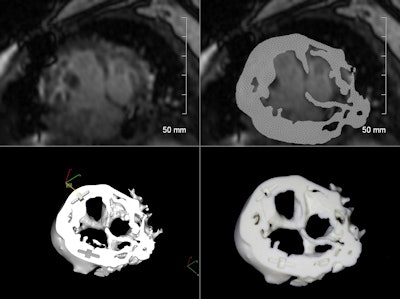

The process begins with acquisition of the MR images on a 1.5-tesla scanner (Signa HDxt 1.5T, GE Healthcare), followed by automated analysis of the DICOM MRI datasets using software (Mimics Innovation Suite 16.0, Materialise).

The software processing enables reconstruction of a 3D rendered model that can communicate with the 3D printer (ZPrinter 450, Z Corporation). The Mimics software employs a thresholding tool to highlight portions of the cardiac MR images that would be reproduced in the model in three imaging planes.

To build the model in a logical way that allowed for a complete intracardiac anatomic assessment of the three cases in the study, the process began with image sequences focused on intracardiac detail rather than blood pool for accurate reproduction of cardiac structures, the authors explained in an abstract.

The MR images are created using a 3D HEART sequence employing a 3D respiratory-navigated balanced steady-state free precession (SSFP) multislab sequence with T2 preparation that provides whole-heart coverage with a high contrast-to-noise ratio between vessels and myocardium, according to the group.

The model images are then reconstructed similar to a short-axis stack with three components (the basal portion, a middle slice containing all four valves, and the apical portion) for improved orientation. This method creates an accurate 3D printed representation of the patient's anatomy with slices set in a familiar orientation and localizing tabs for easy manipulation in the surgeon's hands.

Of course, the job isn't done there. Before the model can be used in surgical planning, Bramlet has to go back to the images, slice by slice, to ensure that what's in the model is actually part of the anatomy and not, for example, blood that the software has mistaken for tissue.